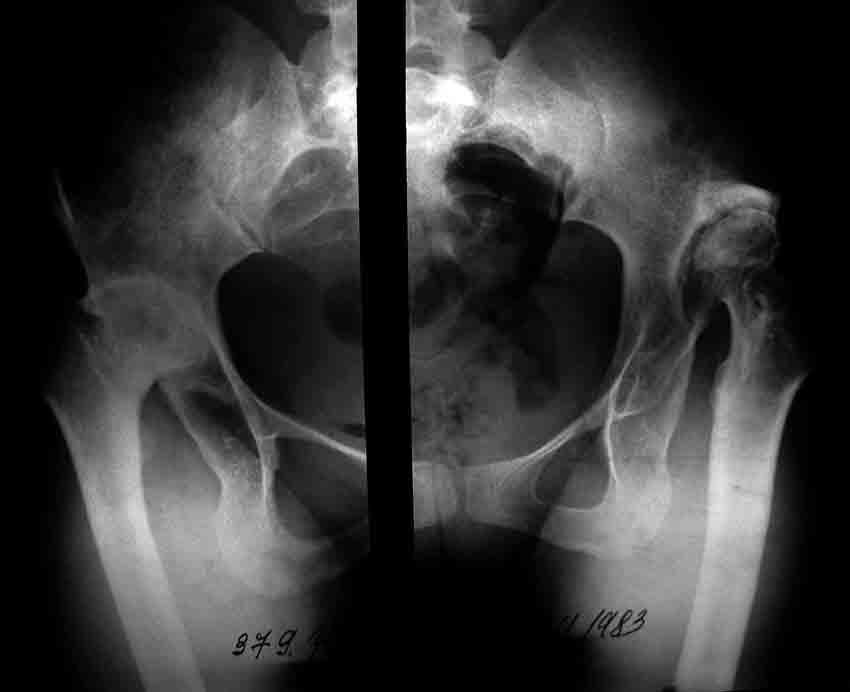

Уважаемые коллеги! Хотелось бы получить совет по тактике лечения. Обратилось 2 девушки - 25 и 26 лет. У обеих грубейшие сгибательные контрактуры тазобедренных суставов.

В одном случае после многократных операций в детстве по поводу врожденных вывихов бедер, в другом - ревматоидный полиартрит. Обе очень маленькие.

Посмотрите на вертлужную впадину при ревматоидном артрите - вертлужная впадина не на месте, нет кости да и качество кости при ревматоидном артрите

плохое. Эндопротезирование в таком случае поможет на очень короткий срок.

Неизбежно и быстро возникнет расшатывание протеза. Повторные операции могут привести к состоянию значительно худшему чем сейчас. Я бы объяснил больной о возможных последствиях прежде чем оперировать.